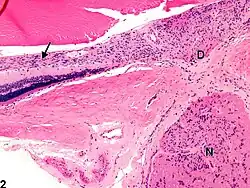

D - disco visual

N - nervio óptico

Los astrocitos son células gliales de gran tamaño y con variadas funciones, incluyendo la acumulación en regiones donde ha habido daño de neuronas. La hiper-proliferación de estos componentes celulares de la neuroglía es el signo histopatológico más importante de un daño al SNC. Los astrocitos pasan por un proceso de hipertrofia e hiperplasia, el núcleo celular aumenta de tamaño y se vuelve vesicular con nucléolos prominentes. El citoplasma, que una vez fuera difuso, se expande y se vuelve brillante bajo la tinción celular e irregular en su morfología, del cual parten numerosos procesos llamados astrocito gemistocítico.